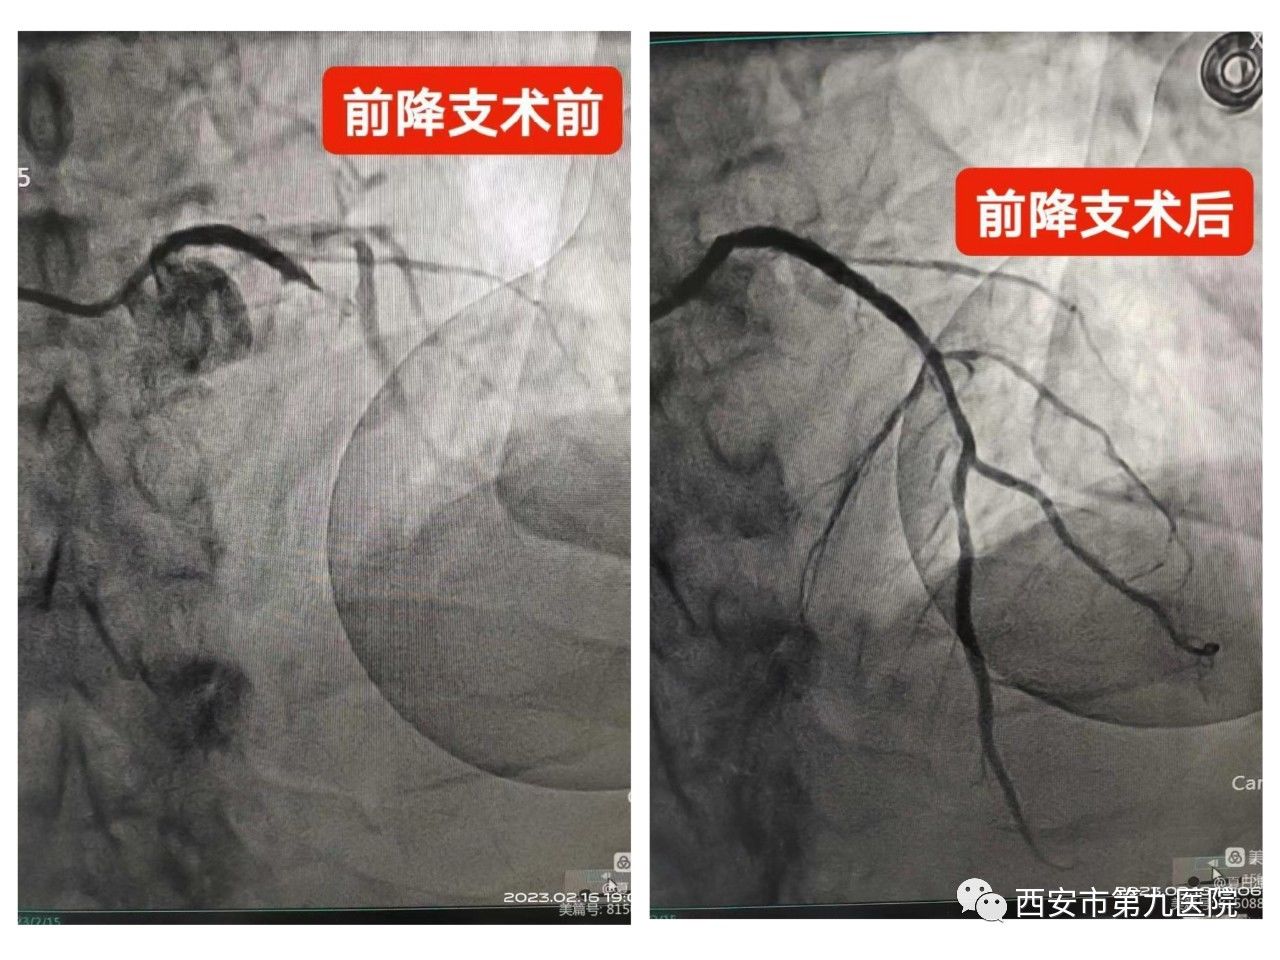

11:02分,患者到达介入中心导管室,心血管病院二科高宇勤主任团队以最快的速度为患者进行急诊冠脉造影术,结果显示患者右主干缺如畸形、前降支闭塞,通过导丝进入球囊扩张后,开通闭塞的冠状动脉,并置入一枚支架,血管完全开通,堵塞的冠脉恢复血流灌注,胸痛缓解,生命体征稳定。